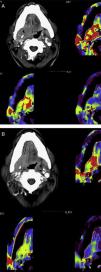

Mediante las imágenes biomédicas podemos diagnosticar, estadificar, controlar y valorar la efectividad de los procedimientos terapéuticos a los que son sometidos los pacientes oncológicos. RECIST (Response Evaluation Criteria In Solid Tumors) es el método para monitorizar el tratamiento mediante medidas unidimensionales de los tumores, obtenidas con técnicas de imagen reproducibles como son la TC, la RM y la PET. Los cambios metabólicos inducidos por los nuevos tratamientos modifican la biología y comportamiento del tumor, con discordancia ocasional entre el estado clínico del paciente y la respuesta medida con RECIST, lo que apunta a la necesidad de incluir pruebas funcionales en la valoración de la respuesta al tratamiento.

Biomedical imaging makes it possible not only to diagnose and stage cancer, but also to follow up patients and evaluate the response to treatment. RECIST (Response Evaluation Criteria In Solid Tumors) provides a method to monitor the response to treatment based on one dimensional measurements of tumors obtained with reproducible imaging techniques like CT, MRI, and PET. The metabolic changes induced by new treatments modify the biology and behavior of the tumor; occasionally, there is a discrepancy between the patient's clinical condition and the response measured by RECIST, which indicates that functional tests need to be included in the evaluation of the response to treatment.